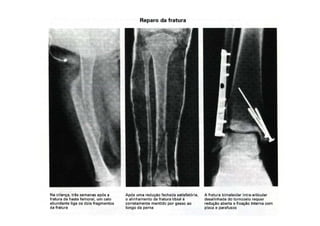

FRATURAS

Tratamento

- Fratura exposta (transformá-la em fechada)

- Fratura patológica (tratamento da fratura e da doença

básica)

- Fratura por estresse (tratamento da fratura propriamente

dita)

1. Provisório

2. Definitivo

figura

31/08/2008 Dr. José Heitor M.Fernandes 26

Tratamento:

- Provisório:

- Tala

- Tração trans-esquelética

- Tração com espuma (por cutânea ??)

- Fixador externo

- Definitivo:

- Redução extemporânea + gesso

- Redução cruenta + osteossíntese